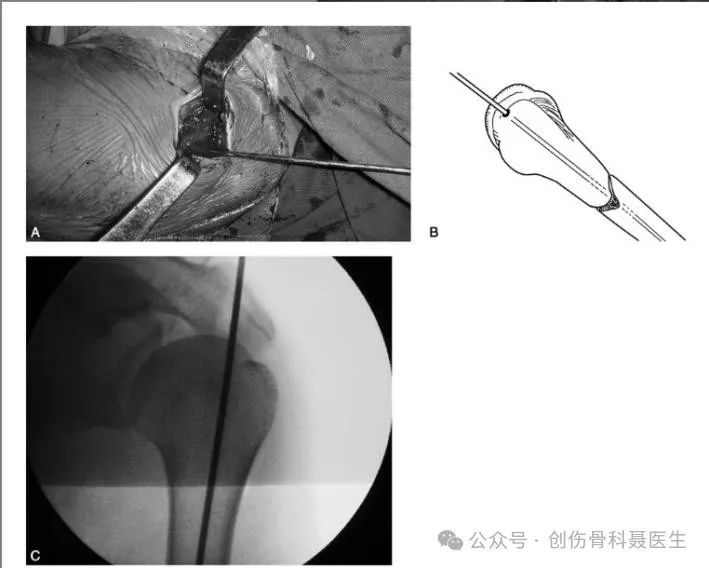

Incision & Entry Point:

Greater Trochanteric Entry Point: The entry point is at the tip of the greater trochanter. On the AP view, it aims toward the medial aspect of the medullary canal; on the lateral view, it aligns with the center of the trochanter and the femoral canal. The trochanteric entry point is often used in obese patients, is technically less demanding, and may be associated with shorter operative times and lower complication rates compared to the piriformis fossa entry.

Piriformis Fossa Entry Point: The entry point is located at the piriformis fossa (the depression medial to the greater trochanter, at the base of the femoral neck), which is the attachment site for the obturator externus tendon. This is the true anatomic starting point aligned with the femoral canal.